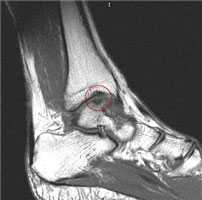

МРТ является ценным инструментом в комплексе диагностики ОХПТК для оценки отека костной ткани, а также выявления скрытых повреждений субхондральной кости и хрящевого покрытия, которые могут быть пропущены при стандартных рентгенограммах или даже КТ. МРТ – самый лучший инструмент оценки для определения стабильности и жизнеспособности фрагмента таранной кости при его отслоении и эта информация может быть решающей в тактике выбора того или иного метода хирургического лечения. Однако, для определения размеров отслоившегося фрагмента таранной кости наилучший метод КТ, так как данные размеров по МРТ могут не соответствовать действительности в сторону переоценки последних. Hepple с соавторами изучив многочисленные данные МРТ диагностики разработали систему классификации ОХПТК на основе этого метода (Табл. 2) [23]. Однако, наиболее широко принятая система классификации, основанная на КТ-это классификация Ferkel и Sgalione (Табл. 3; Рисунок 4) [24]. Классифицировать ОХПТК также возможно выполнить интраоперационно, на основе артроскопических данных о состоянии остеохондрального поражения. Наиболее широко используется система Ferkel/Cheng (Табл. 4) [25], эта система классификации, в отличие от обычных рентгенограмм, КТ и МРТ, лучше всего взаимосвязана с исходами лечения пациентов.

а. схематическое изображение рассекающего остеохондрита таранной кости. б. на МРТ и рентгенограммах определяется рассекающий остеохондрит.

На МРТ выявляется рассекающий остеохондрит с отделением костно-хрящевого фрагмента от таранной кости.